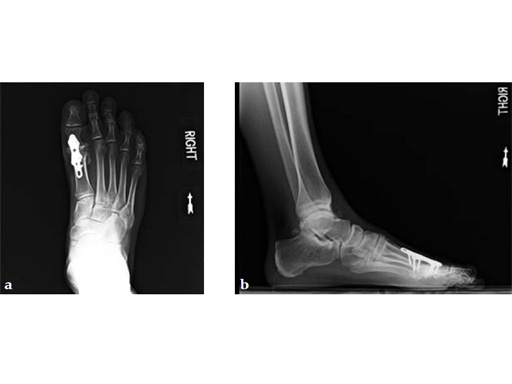

Case 2: First MTP fusion plate

A 38-year-old man presented for opinion after two attempts to fuse the big toe MTP joint. The AP view is significant for luscency at the joint line. The lateral view is notable for loosening of the hardware and malposition because of the dorsiflexion built in to the precontoured implant. Revision was planned using a 0 variable angle locking/compression hallux MTP plate.

Case provided by Michael Castro, Scottsdale, Arizona

At 10 weeks postoperatively (see Fig. 2ab) the patient had no pain with weight bearing. The lateral view demonstrates improved position of the toe using a 0angle plate.